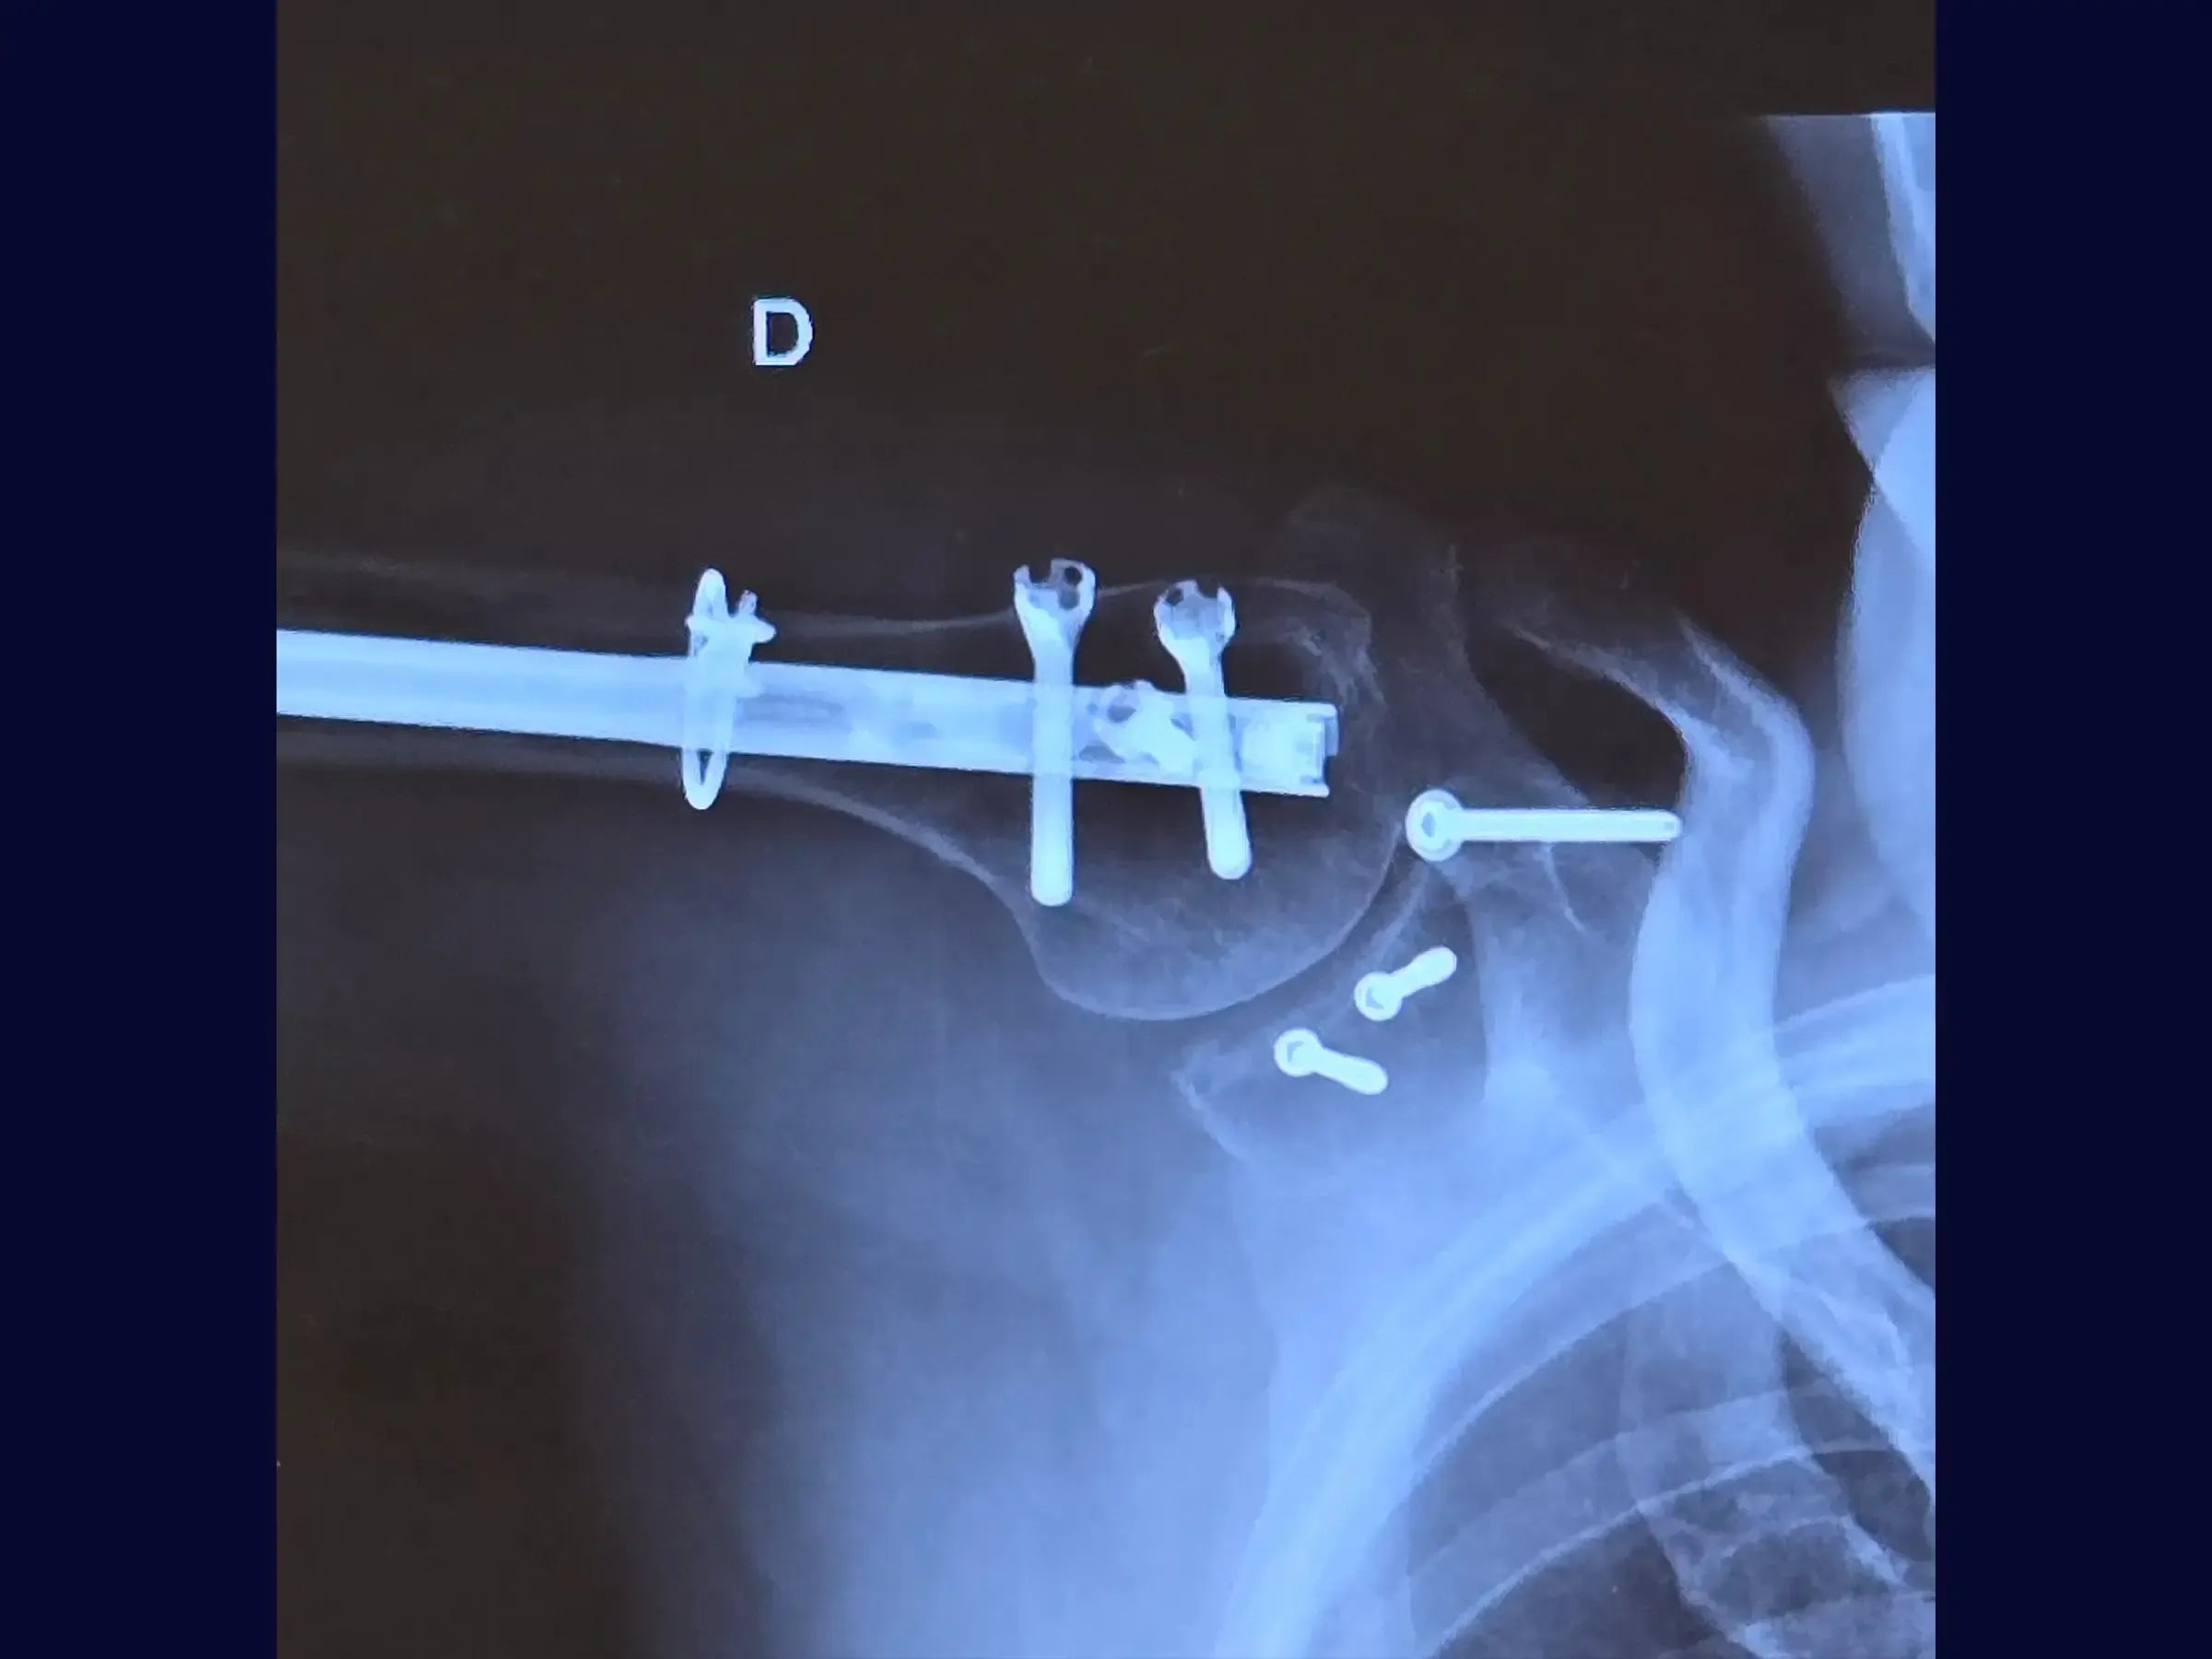

- Osteosíntesis de fracturas glenoideas con tornillos de compresión.

- Osteosíntesis efectiva: demostración de visualización transversal del fragmento y técnica de fijación con tornillos de compresión para la estabilidad de la fractura glenoidea.